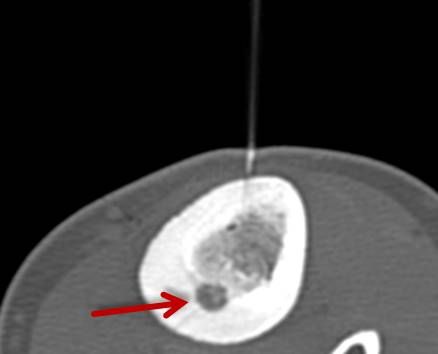

Die minimalinvasive Thermoablation ist auch eine Therapieoption für Lungentumore. Damit ein Lungentumor mit diesem Verfahren effektiv und sicher behandelt werden kann, sollten bestimmte Bedingungen (wie Größe, Anzahl und Lage) erfüllt sein. Ob diese Voraussetzungen gegeben sind, wird das Vorgehen vor der Therapie mit Kollegen aller für diese Fragestellung relevanten Fachdisziplinen besprochen.

Abbildung: Bei der perkutanen Thermoablation von Lungentumoren werden spezielle Applikatoren unter CT-Bildgebung in den Zieltumor eingebracht. Durch Hitze wird der Tumor dann zerstört.